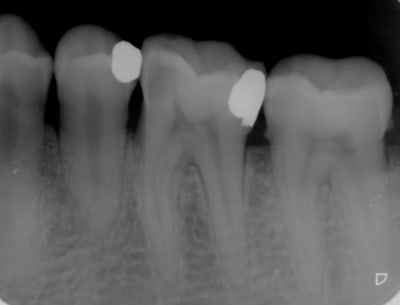

Pour infos, dévitallisation sous digue avec obturation au sealite et condensation verticale à chaud ( 4 canaux).

il y avait un epaississement au niveau de la racine D avec un début de furcation avec retraction de la corne pulpaire distale en regard de l'amalgame ancien signant une pulpite chronique

Tu utilises un localisateur d'apex ? Sur la radio ça me parait un peu court en distal... mais bon c'est une radio.

Oui, j’utilise le morita mini root, très fiable je trouve.

En distal , je suis un peu court, mais ça ne doit pas occasionner plus de douleurs que ça, voir aucune.

Cela dit, une radio de contrôle désaxée aurait permis de mieux voir les 2 canaux distaux.

Quelle est le diamètre d'obturation en distal? 25/100? Parce qu'on voit clairement que le canal s'élargie dans le tiers apicale, et qu'il n'est pas assez obturé... En général il faut obturer avec au moins du 40/100 les canaux distaux des molaires mandibulaires.

Mais on est d'accord, la sous-obturation n'explique pas la douleur.